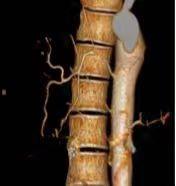

随着CT技术的发展,CT血管成像(CTA)的应用越来越广泛,本课题主要探讨支气管动脉CTA检查影响其阳性显示的主要因素以及本地区普通人群BA分布图。支气管动脉(BA)是肺支架组织的营养血管,其多发自胸主动脉,走行于纵膈间隙,攀附于支气管壁经过肺门进入肺组织,形成毛细血管网并营养周围组织。BA本身管径细小(1-2mm),走行迂曲,行程不定;起源、开口位置及数目变异大,若能在实施介入治疗前对BA的分布、形态及与疾病的关系有一全面了解,将对介入治疗提供重要帮助。

研究认为,支气管动脉作为肺部介入手术的主要靶血管,在实施介入手术前,对有肺部基础疾病的患者行支气管动脉CTA检查,支气管动脉能都得到阳性显示,同时能提供一个非侵入性评价支气管动脉及其肺部病变的有效方法。

因为支气管动脉起源变异明显,该科研课题的应用,术前能把支气管动脉的起源及走行显示的更清楚,更有利于提高手术成功率,减少术后复发的机会,降低医疗风险,是一种安全有效、经济实用的方法,该技术值得临床推广应用!